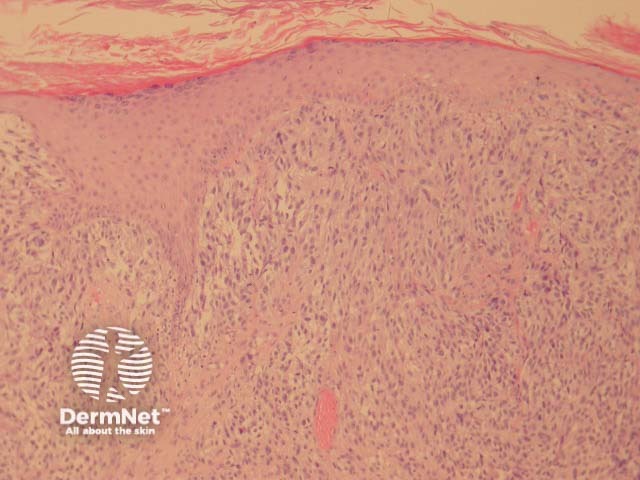

Most melanomas have an initial radial growth phase within the epidermis and sometimes within the papillary dermis (figure 1, 2), which may be followed by a vertical growth phase with deeper extension (figures 3, 4). The exception to this is nodular melanomas, which either skip the radial growth phase or the radial phase is rapidly overrun by the vertically growing tumour. It is also possible that they arise within dermal melanocytes. It has been proposed that lesions in the radial growth phase are incapable of metastasis, however there are numerous examples of thin melanomas that have behaved aggressively, even without convincing evidence of vertical growth.

Figure 1

Figure 2

Figure 3

Figure 4

Superficial spreading melanoma (SSM) is the most common melanoma variant. These tumours are most commonly found on the back in males and legs in females. Histologically they are characterised by atypical epithelioid melanocytes, found singly or in clusters, scattered throughout the epidermis (known as ‘buckshot scatter’). Tumour cells have abundant cytoplasm, nuclear pleomorphism and prominent nucleoli. Melanocyte proliferation can be seen extending over the tips of the papillae in continuity from one rete ridge to another. Adnexae may be involved. Thinning or consumption of the epidermis may occur. Invasive dermal components show lack of maturation and varying degrees of atypia. See Figures 10, 11, 12, 13, 14, 15.